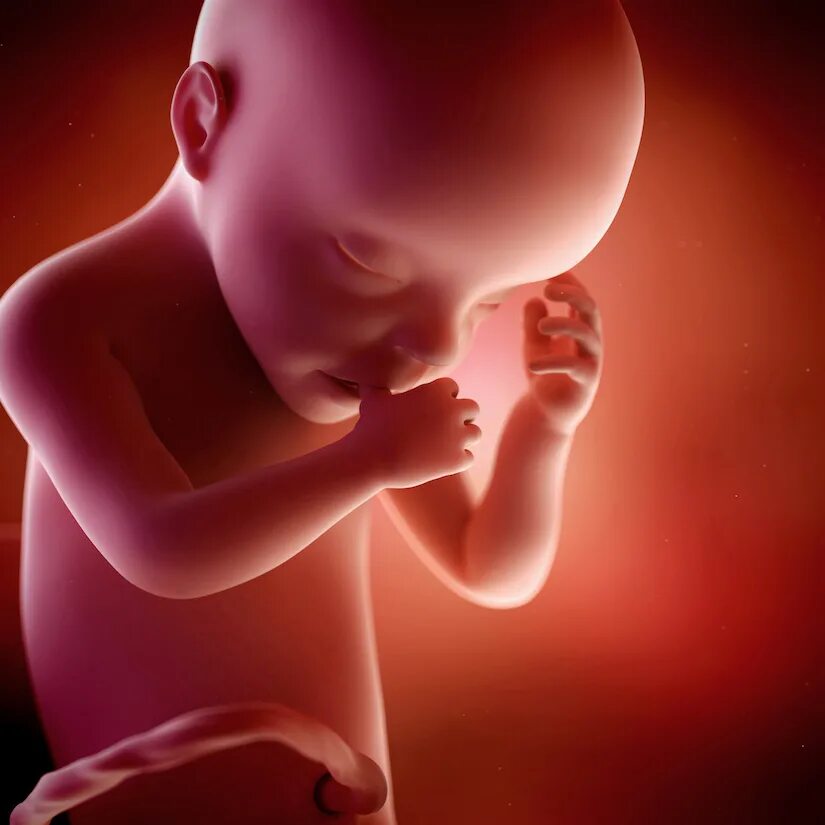

Развития плода 30 недель